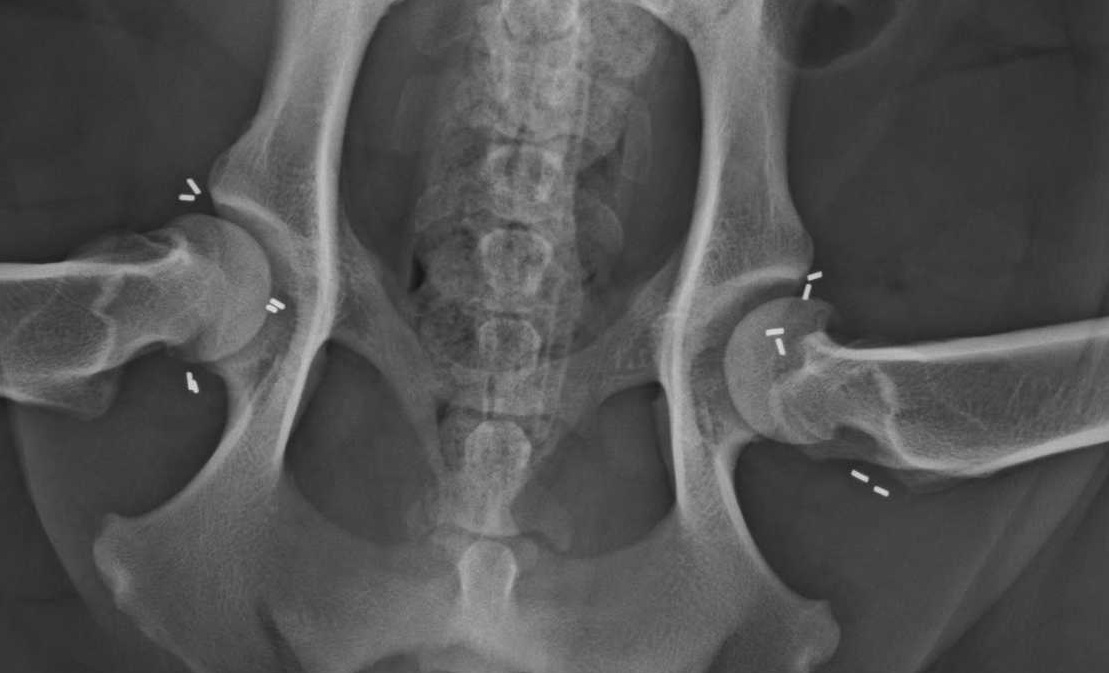

Die Goldakupunktur ist eine Dauerakupunktur mit Golddrahtstückchen, die durch die permanente Einwirkung auf die Akupunkturpunkte und -meridiane den Stoffwechsel erkrankter Gelenke und der Muskulatur verbessert und dadurch zu einer Schmerzlinderung oder -befreiung führt. Hierbei werden stiftförmige Stücke eines hochkarätigen Golddrahtes, in manchen Fällen auch Platinimplantate, an die Akupunktur- und Schmerzpunkte implantiert. Die Methode ist minimalinvasiv und bereitet dem Patienten daher keine Operationsschmerzen. Die Implantate wachsen ohne weitere Probleme im Gewebe ein und verbleiben ein Leben lang an der gewünschten Stelle. Diese schonende dauerhafte Schmerztherapie kann bei Gelenkserkrankungen z.B. Hüftgelenksdysplasie, Ellenbogendysplasie, Kniegelenksarthrosen, Wirbelsäulenveränderungen und deren Folgen eingesetzt werden. Die Methode wurde in den USA von DVM Terry E. Durkes Ende der 70er Jahre entwickelt.

Wir arbeiten mit dieser modifizierten Methode, die als ganzheitliche Orthopädie zu verstehen ist, seit nunmehr 16 Jahren erfolgreich in unserer Praxis. Die vorhergehende umfassende Diagnostik mit einer ausführlichen Gangbildanalyse und der Triggerpunktdiagnostik (Schmerzpunktuntersuchung) erfasst alle relevanten Schmerzen, auch die, die sich nur aus der Entlastung der veränderten Gelenke und damit einer Überbelastung in die anderen Gelenke ergeben. Weiterführend werden digitale Röntgenbilder angefertigt.

In der Gangbildanalyse wurde die Lahmheit hinten links und vorne rechts bestätigt. Cash lief sehr schwerfällig und zeigte eine deutliche Hüftrotation auf der rechten Seite. Die Ellenbogen waren beide stark ausgestellt und Cash schleift über die Vorderfüße. Ein Schwingen im Rücken lässt Cash nicht zu und hält sich in der Rückenmuskulatur sehr fest. Die Untersuchung der Triggerpunkte war für Cash besonders im Rücken, an den Hüften, den Knien und den Ellenbogen sehr unangenehm. Nach der Blutuntersuchung, die keine Abweichungen ergab, und der folgenden in einer leichten Sedation ausgeführten ausführlichen Röntgendiagnostik wurden alle Befunde (beidseits hochgradige HD, hochgradige Ellenbogenarthrose rechts und links, Knie links post OP) und die mögliche Prognose für Cashs Schmerzbehandlung besprochen. Die Besitzer entschieden sich für eine Goldakupunkturbehandlung ihres Hundes.

Vor einem Monat wurde uns „Yelle“, eine 4-jährige Cocker-Spaniel-Hündin, vorgestellt. Durch die Gangbildanalyse, der Untersuchung der Triggerpunkte und das folgende Röntgen wurde schnell klar, dass Yelle durch eine sehr lose schmerzhafte Hüfte ein deutlich verändertes Gangbild zeigte. Die Besitzer entschieden sich daher frühzeitig für eine Goldakupunktur, um Folgeschäden an den anderen Gelenken zu minimieren. Die Kontrolluntersuchung nach der Goldimplantation verlief sehr positiv - Yelle will spielen und toben. An diesem Punkt ist es wichtig, dem Muskelaufbau Zeit zu geben und den Hund noch nicht zu viel toben zu lassen. Eine geregelte Bewegung und eventuelle physiotherapeutische Unterstützung hilft, das Gangbild zu stabilisieren.